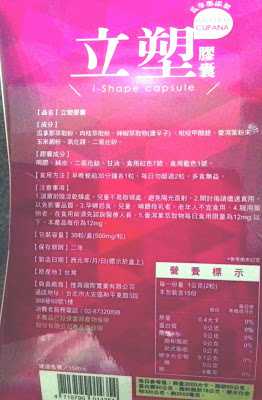

Supercut塑魔纖立塑膠囊的成分有:瓜拿那萃取粉、肉桂萃取粉、辣椒萃取物(唐辛子)、吡啶甲酸鉻、番瀉葉粉末、玉米澱粉、氧化鎂、二氧化矽。

之前上過相關課程,成分表是依照每項成分的多寡來排列順序,排在最前面的就是產品的主要成分!

那我就跟大家分享瓜拿那萃取粉、肉桂萃取粉和辣椒萃取物吧

瓜拿那萃取和辣椒萃取是可以幫助纖體瘦身常見的營養素!

1.「瓜拿那」是原產於亞馬遜流域的一種藤蔓植物,富含酵素可以幫助排便順暢,並且能抑制脂肪分解酵素,此外也有降低食慾的效果喔~~萃取物中含有天然咖啡因,可以提高新陳代謝率以及排出多餘水分!

2.「辣椒萃取物」則是可以幫助體內脂肪燃燒、增加卡路里的消耗,達到防止脂肪積聚的效果

3.「肉桂萃取物」看到肉桂,就想到麥當勞的蘋果派或是手掌麵包,雖然很多人很害怕那味道,但艾哥愛死肉桂了!!!!肉桂在古代被視為是最有價值的東方香料之ㄧ,中世紀時,肉桂的聲望僅次於昂貴的黑胡椒,除了香料和薰香價值, 傳統上肉也被用來治療消化不良、脹氣、關節疼痛、出血和經痛,研究也指出肉桂可以促進新陳代謝喔

食用方式:早晚餐前30分鐘各1粒,每日不超過2粒。(多食無益)

番瀉葉萃取物每日食用限量為12mg以下,

番瀉葉萃取物每日食用限量為12mg以下,